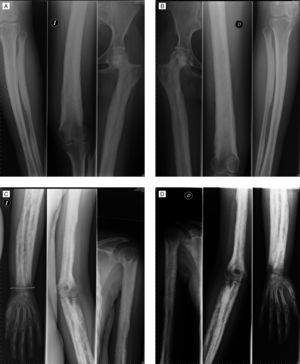

Mujer de 32 años de edad con antecedentes personales de hipotiroidismo en tratamiento sustitutivo, menstruante y sin hijos. Refería no tener antecedentes familiares de enfermedad osteoarticular. Relataba haber sido diagnosticada, en su país de origen, a la edad de 4 años de distrofia muscular. No se disponía de informes ni de historia previa en este sentido, refiriendo la paciente que dicho diagnóstico se había realizado por retraso en la adquisición de la edad de deambulación y que no se le había realizado biopsia muscular ni aportaba ningún estudio específico. Consultaba por artralgias mecánicas de largo tiempo de evolución, sin tumefacción articular, sin rigidez matinal y refería que desde hacía años los miembros superiores habían aumentado de tamaño y que el diámetro de muslos y piernas también habían aumentado. Por todo esto había acudido originalmente al Servicio de Neurología de nuestro hospital, donde tras la realización de analítica con CPK normal, electromiograma sin datos de miopatía y estudio de resonancia magnética de cintura pelviana sin datos de miositis, nos la remiten para estudio. A la exploración destacaba ausencia de sinovitis, recorridos articulares pasivos y activos limitados de forma global, fuerza muscular normal y aumento de longitud de miembros superiores. También llamaba la atención una marcha con cierta oscilación de la pelvis, lordosis lumbar exagerada y balanceo laterolateral. Los reflejos tendinosos eran normales y no había deformidad en los dedos de los pies ni de las manos. El estudio radiológico simple realizado mostró engrosamiento cortical y esclerosis de las diáfisis de los huesos tubulares con osteoesclerosis irregular y heterogénea con áreas moteadas de radiolucencia con mayor afectación endóstica que perióstica y estrechamiento de los canales medulares (fig. 1). Las epífisis estaban respetadas radiológicamente. Densitometría de cuello femoral Z-score +6,2 DE.

DiscusiónLos hallazgos radiológicos son sugestivos de displasia ósea. El número de displasias óseas es alto y no existe un consenso generalizado sobre su nomenclatura y clasificación; no obstante, con la expansión del conocimiento del genoma humano, para aquellas en las que el locus genético es conocido, ahora es posible la tipificación genética exacta. En este caso la afectación diafisaria con respeto de las epífisis hace pensar que se trata de una displasia del grupo hiperostosis craniotubular, siendo la más frecuente de las mismas la displasia conocida con el epónimo de enfermedad de Camurati-Engelmann. Se trata de una displasia con engrosamiento progresivo de las diáfisis de los huesos largos de forma bilateral y simétrica que a medida que avanza afecta a las metáfisis pero no a las epífisis1. El cráneo también puede estar afectado pero éste no era el caso de nuestra paciente. La presentación se suele dar en la infancia con dolor articular, debilidad muscular, marcha de pato y fatigabilidad. Su patrón de herencia es autosómica dominante y se debe a una mutación en el gen del TGFβ1 (transforming growth factor β1), de la cual se conocen 10 variantes2. El estudio genético en nuestra paciente confirmó la sospecha diagnóstica para la mutación c.652C→T, p.Arg218Cys, mutación ya descrita previamente para esta enfermedad2.